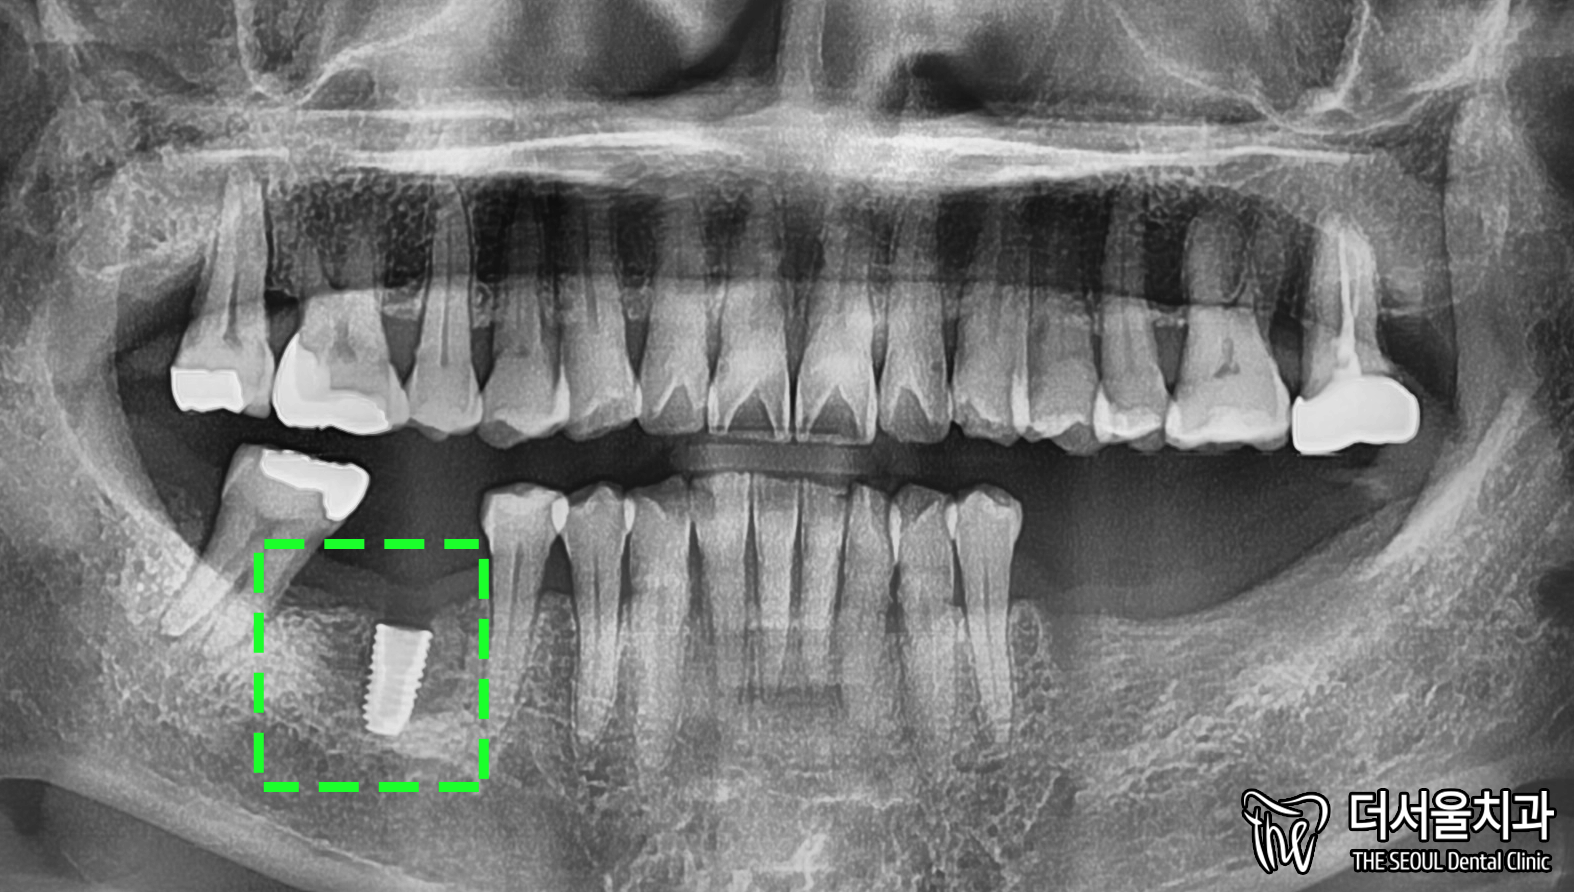

46번 먼저 처리하기로 하며

30번대는 추후에 해결하기로 했습니다.

계획에 맞춰 치아 뿌리에 해당되는

‘픽스처’를 심었습니다.

워낙 잇몸뼈는 좋은 편이 아니었기에

골결합 시간을 충분히 두었는데요.

다행히 뼈와 붙는데 3개월이 걸렸습니다.

4개월 정도 걸릴 것이라 예상했었는데 말이죠.

뼈와 튼튼하게 잘 붙은 것을 확인 후,

본뜨는 과정을 진행합니다.